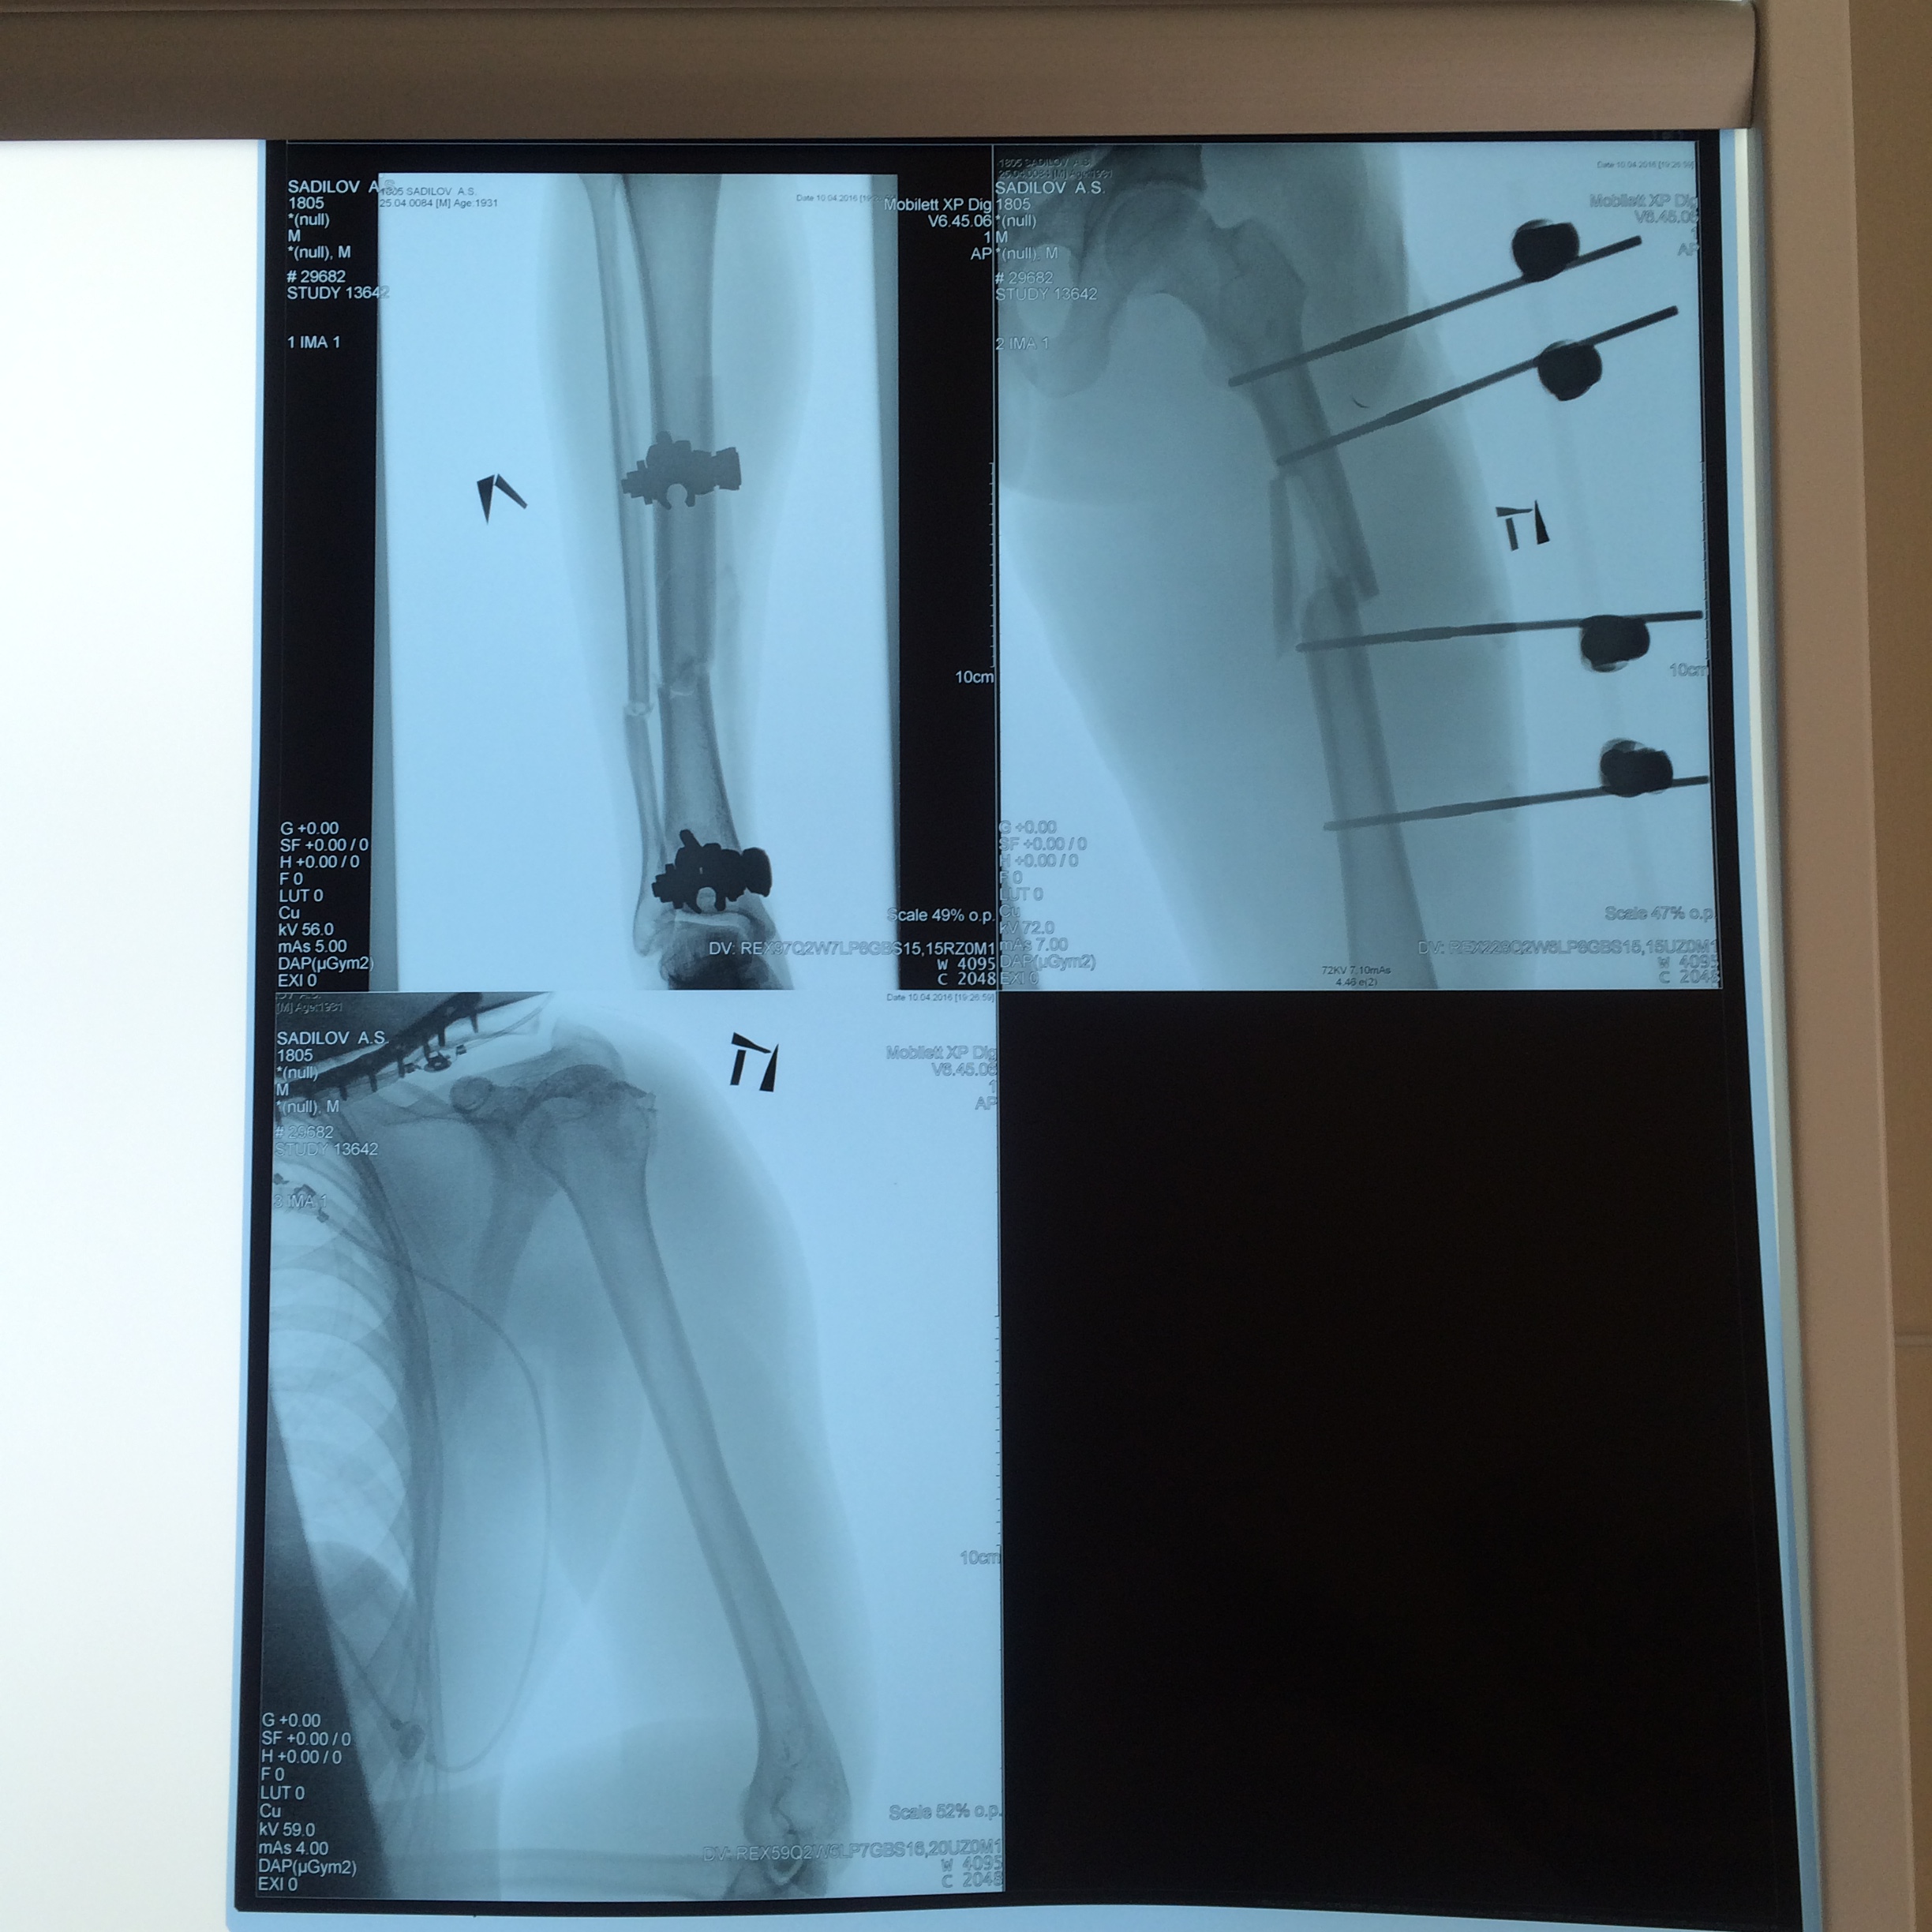

"- Ваша поддержка мне очень помогла, я чувствую себя лучше, вчера меня перевели на амбулаторное лечение. Самым лучшим подарком для меня было то, что из больницы я вышел самостоятельно, на своих ногах.  Выражаю особую благодарность моим врачам Александру Валентиновичу Шевченко, Евгению Витальевичу Украинскому, Ольге Викторовне Олифировой.  Отдельная благодарность  Президенту Мотоциклетной Федерации России Александру Васильевичу Джеусу за Вашу помощь и участие!"

...Артем стесняется и просил нас не писать диагноз, а он достаточно большой. В общем кто хотел и хочет помочь, помогите. Так как Артему теперь предстоит длительный период лечения и восстановления после травмы.